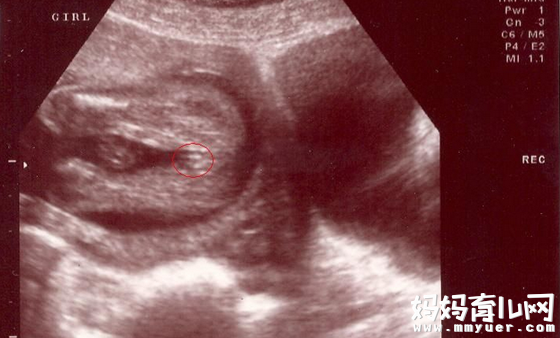

女宝宝的b超图:

三条白线是明显的女宝特征,如果没有看到明显的三条白线,就看两腿之间有没有突出的东东,且中间有小凹槽的,就是女宝